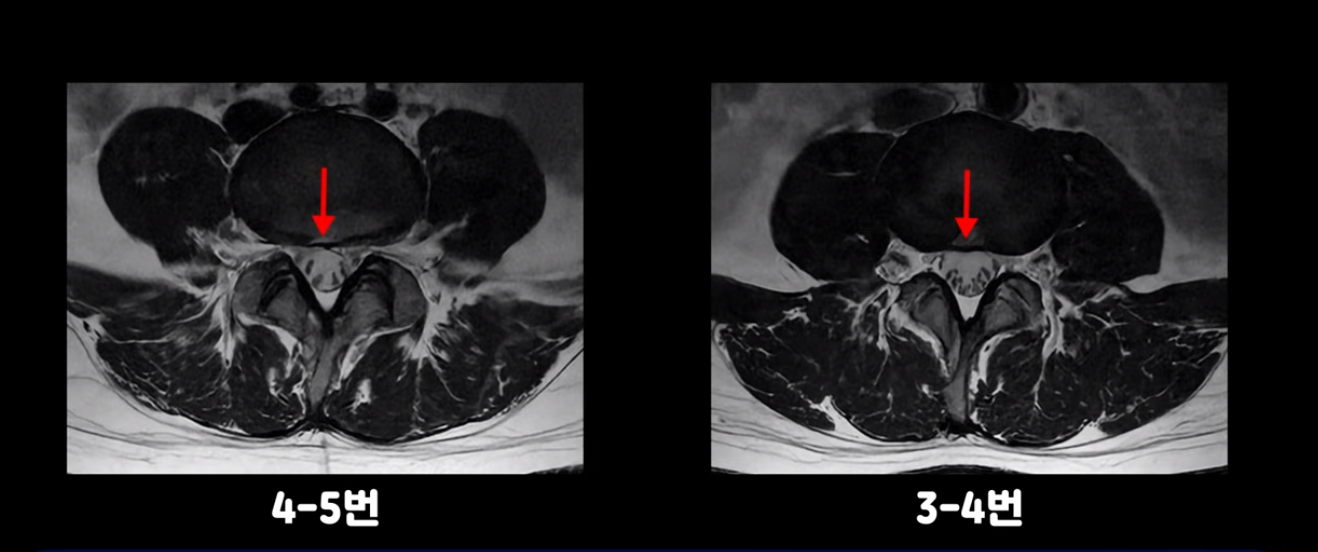

4번 5번과 3번 4번 마디도 디스크가 중앙으로 살짝 밀려나와있지만 최근에 섬유륜이 찢어진 것도 아니고, 신경 다발을 누를 정도로 심하게 밀려나와 있는 것도 전혀 아닙니다.

양쪽 신경 가지가 빠져나가는 추간공도 충분히 넓어서 신경학적 방사통을 일으킬 여지가 없습니다.